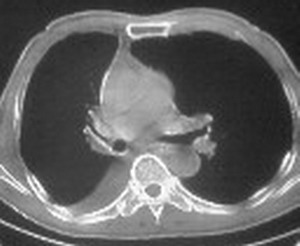

标题: CT6943:[讨论]胸部,M/67Y,体检发现。

ct值约12hu。

ct值约12hu

右肺下叶支气管阻塞,右下叶不张,考虑中心型肺癌伴下叶不张

先考虑:右下肺中心型肺癌伴下叶肺不张、胸腔积液

右肺下叶支气管闭塞,中间段支气管狭窄,下叶不张,胸腔及叶间积液.中心型肺癌伴下叶肺不张.胸腔和叶间积液.

右肺下叶支气管闭塞,伴下叶实变不张。建议增强及纤支镜。

右肺下野后部均匀低密度影,边缘锐利,前缘外突(不支持肺不张),纵隔内未见明显肿大淋巴结,右下肺门结构显示欠清,临床资料太过简单,考虑右侧后胸部包裹性积液。其他待排。建议密切结合临床其他检查。

考虑右下肺中心型肺癌伴下叶肺不张、胸腔积液。